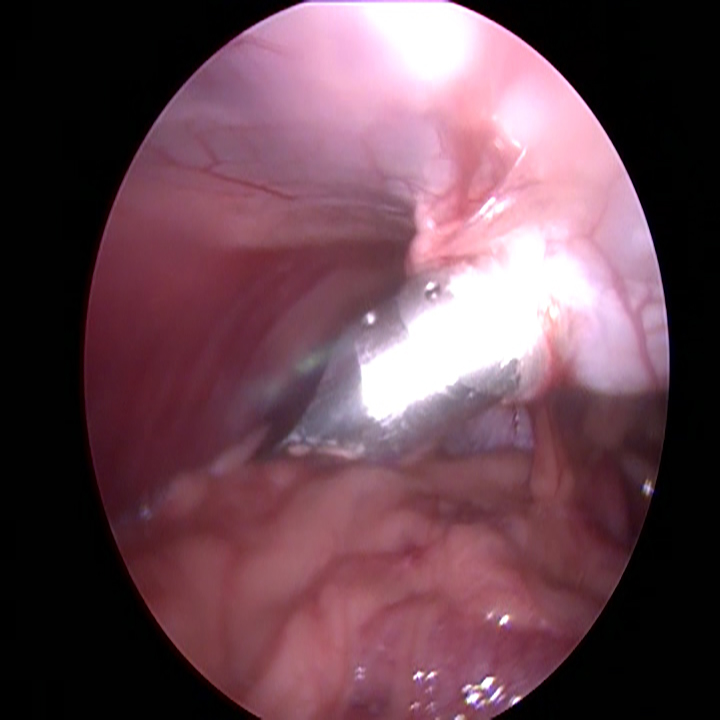

Wanneer alle trocars geplaatst zijn, kantelen we de operatietafel naar voren en leggen we de patiënt op haar zij. Dan gaan we op zoek naar de linker eierstok. Doordat de milt eroverheen ligt kan dit soms wat meer moeite kosten. Eenmaal gevonden, branden we de ophangbanden en bloedvaten van het ovarium door. Hierbij moet ervoor gezorgd worden dat er ver genoeg van de nieren en de buikwand af gewerkt wordt, om hitteschade te voorkomen. De eierstok wordt via het gat bij het bekken verwijderd. Na het controleren van de plek waar de eierstok verwijderd is en na het opnieuw plaatsten van de achterste trocar, wordt de andere kant gedaan.

De daadwerkelijke laparoscopische sterilisatie, in beeld: